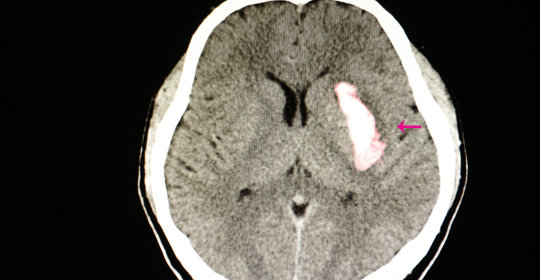

橋腦出血:突發症狀、治療攻略一覽

丘腦出血:瞭解出血病因與科學治療